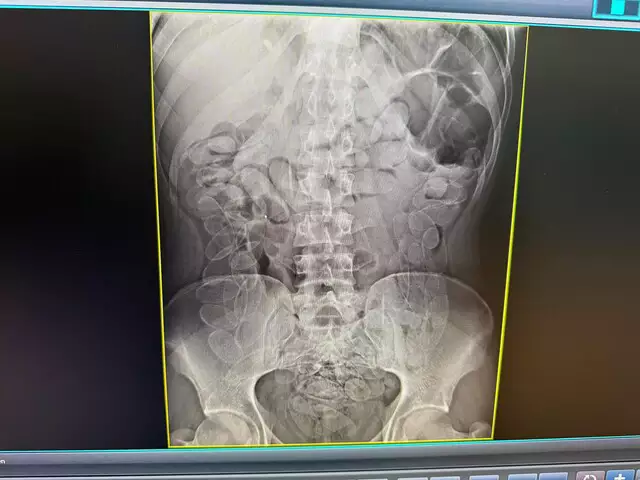

Um boliviano de 24 anos foi preso, em flagrante, ao engolir 90 cápsulas de cocaina. A ocorrência foi registrada em Corumbá, em uma abordagem de rotina no Posto de Fiscalização Esdras.

Diante disso, o rapaz foi encaminhado à Santa Casa de Corumbá, onde permaneceu sob acompanhamento médico até a expulsão segura do material.